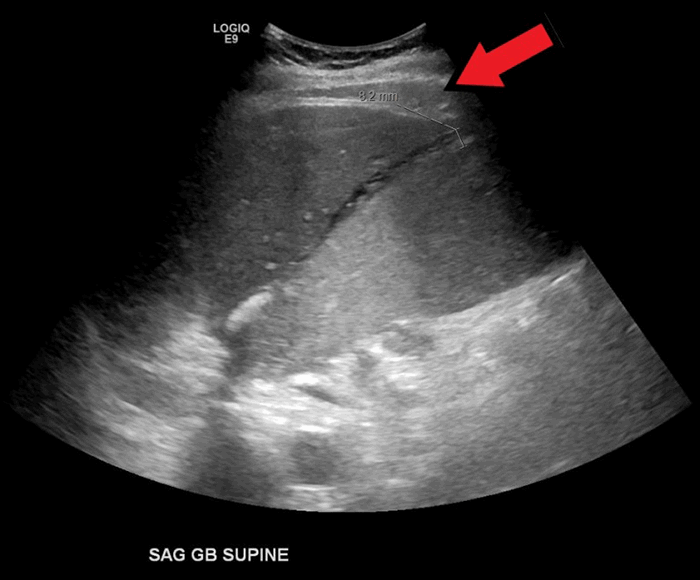

A 68-year-old male with no known history of cholecystitis or biliary disease presented to the emergency department with the complaint of diffuse epigastric pain. His medical history was significant for Roux-en-Y gastric bypass, noninsulin dependent diabetes, hypertension, acid reflux, and coronary artery disease status post a coronary artery bypass graft, for which he takes a daily baby aspirin. At that time, an evaluation for acute coronary syndrome was negative and he was discharged home with pain medication. There was no evaluation for abdominal pathology at this time. Three days later he again presented to the emergency department due to progression of his epigastric pain. At this time a diagnosis of acute cholecystitis was made by ultrasound with incidental finding of ascites (Figure 1). He had a significant leukocytosis (38.7 k/ul) and lactic acidosis (3.2 mg/dL). Given the severity of his illness, further imaging was obtained. A computed tomography (CT) scan demonstrated massively distended gallbladder with a blush of contrast in the lumen of the gallbladder concerning for active hemorrhage (Figure 2), as well as a significant amount of hemoperitoneum (Figure 3). The patient subsequently became hemodynamically unstable and was transported to a quaternary care center. He transiently responded to resuscitation with blood products but ultimately decompensated again before being emergently transported to the operating room. A midline exploratory laparotomy was performed that demonstrated a large amount of blood in the peritoneal cavity. All four quadrants were packed with lap sponges and old blood was evacuated. The bowel appeared to be decompressed. The gallbladder was found to be massively distended and filled with blood. One necrotic area had perforated, and blood was actively spraying into the abdomen. No other sources of bleeding were seen. The gallbladder was sharply opened and packed. A clear source of bleeding was not seen in the gallbladder but was controlled with packing. At this time pulses were lost and cardiac monitor with rhythm strips showed ventricular tachycardia. Despite attempts at resuscitation with advanced cardiac life support protocol, the patient ultimately expired, with a presumptive diagnosis of cardiogenic shock due to acute blood loss. An autopsy was not performed per patient family wishes.

Figure 1. Ultrasound image demonstrating distended gallbladder with thickened wall and ascites. Arrow head shows the distended gallbladder. Arrow shows ascites.

In the cases we reviewed, right upper quadrant ultrasound and CT scan of the abdomen and pelvis were the most common initial imaging studies in these patients. Ultrasound findings include distended gallbladder, wall thickening and pericholecystic fluid collection, with the most frequent diagnosis being acute cholecystitis. One study reported ultrasound finding of an intraluminal pulsatile mass.6 CT scans were performed in 11 patients, with only four of those demonstrating active intraluminal extravasation of contrast.4,5,9 A pseudoaneurysm of the cystic artery was present in three patients.10 Other findings suggestive of hemorrhage on CT scan included hemoperitoneum (one patient), blood clots in gallbladder (one patient), and heterogeneous intraluminal fluid (one patient) were described in three patients. Two patients had no significant CT findings. The initial imaging study of choice for biliary disease is ultrasonography.11 However, ultrasound does not appear to be ideal for differentiating between acute and hemorrhagic cholecystitis. The retrospective review study reported ultrasound findings on 19 acute cholecystitis patients with pathological findings of hemorrhage cholecystitis.12 They reported that ultrasound findings suggesting hemorrhagic cholecystitis included intraluminal membrane, focal gallbladder wall irregularities and nonshadowing, nonlayering intraluminal echoes.12 However, these findings were not present in the other 14 patients we reported here. Notably, because the retrospective study was published in 1987, CT scans might not have been widely available. We conclude that CT scan is useful in the diagnosis of hemorrhagic cholecystitis.